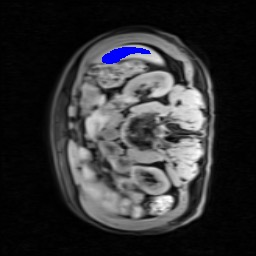

Transformers have made remarkable progress towards modeling long-range dependencies within the medical image analysis domain. However, current transformer-based models suffer from several disadvantages: (1) existing methods fail to capture the important features of the images due to the naive tokenization scheme; (2) the models suffer from information loss because they only consider single-scale feature representations; and (3) the segmentation label maps generated by the models are not accurate enough without considering rich semantic contexts and anatomical textures. In this work, we present CASTformer, a novel type of generative adversarial transformers, for 2D medical image segmentation. First, we take advantage of the pyramid structure to construct multi-scale representations and handle multi-scale variations. We then design a novel class-aware transformer module to better learn the discriminative regions of objects with semantic structures. Lastly, we utilize an adversarial training strategy that boosts segmentation accuracy and correspondingly allows a transformer-based discriminator to capture high-level semantically correlated contents and low-level anatomical features. Our experiments demonstrate that CASTformer dramatically outperforms previous state-of-the-art transformer-based approaches on three benchmarks, obtaining 2.54%-5.88% absolute improvements in Dice over previous models. Further qualitative experiments provide a more detailed picture of the model's inner workings, shed light on the challenges in improved transparency, and demonstrate that transfer learning can greatly improve performance and reduce the size of medical image datasets in training, making CASTformer a strong starting point for downstream medical image analysis tasks.